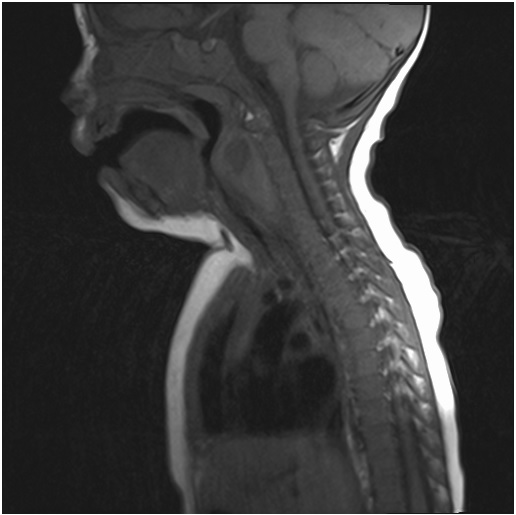

Figure 1: MRI of the neck showing retropharyngeal abscess overhelming larynx and obturated piriformn sinuses.

figure 1